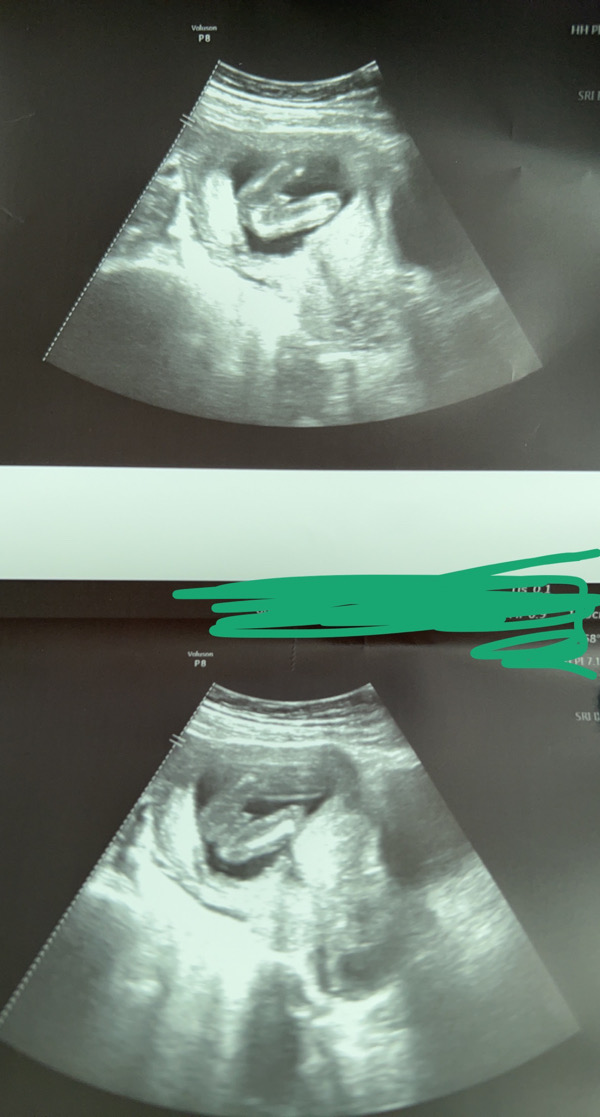

بنات بوريكم سونار و عطوني رأيكم

🌚🤝لعبتي السونار 🤣🤣⏳

كنه ولد زي سوناري 🌚😍😍💙

ولد